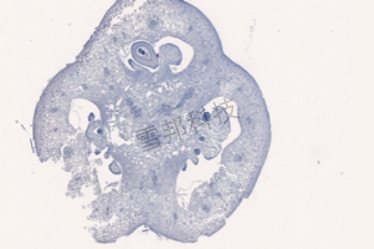

甲苯胺蓝(软骨)

软骨基质对甲苯胺蓝的异染性,是因为软骨基质的主要成分是软骨黏蛋白、多糖物质,而酸性硫酸根与嗜碱性染料有亲和力。此法用于显示新生骨组织钙盐沉积,成骨细胞数目统计,观察软骨退变.